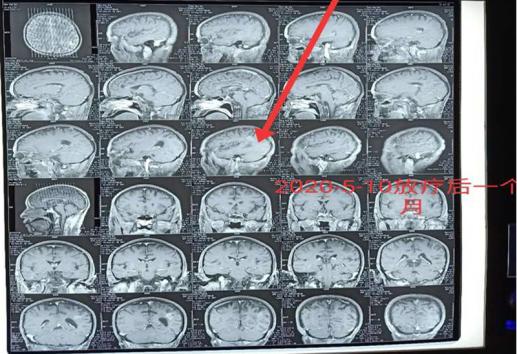

“许大爷肿瘤多发转移了,我们不建议采取手术治疗了,但是,目前大爷头痛明显,针对头部转移灶我们可以使用立体定向放疗—陀螺刀治疗,同时啊,脑袋有多发的转移病灶,我们还需要在此基础上加上全脑放疗,以增加对头部肿瘤的控制效果。”唐三元主任表示。

哪些情况适合开展陀螺刀治疗呢?唐三元主任解释,陀螺刀最适合的就是对于那些肿瘤比较小,个头比较局限,位置又比较深的肿瘤,像许大爷这样的脑转移瘤就非常适合该项技术。其他的还比如,不能去开刀或者是不愿意开刀的肺癌,不能手术的肝癌等等都可以根据情况开展局部放疗也就是陀螺刀治疗。当然,对于那些空腔脏器上的肿瘤如食道癌、胃癌、肠癌还是不能行该项技术的。肿瘤太多的话,像这位许大爷,我们就在陀螺刀的基础上还加上了全脑放疗,因此,才取得了这么好的效果!